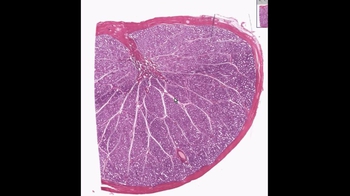

27. The Reproductive System

Anatomy of the Male Reproductive System